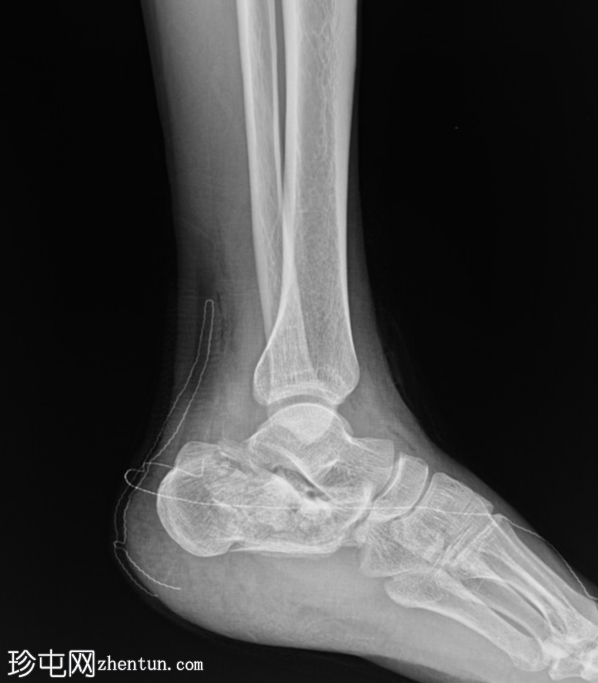

正位片